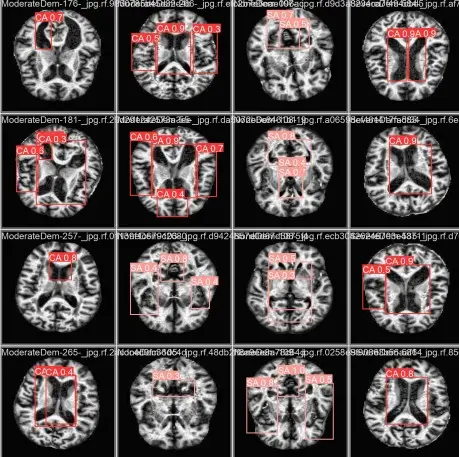

Imagem mostra cérebro visto por meio de exame de ressonância magnética.

Legenda: Conjunto de imagens de ressonância magnética cerebral, mostrando diferentes seções e angulações do cérebro humano.

Foto: Reprodução/Estudo IFCE.

A análise detalhada das imagens de RM, incluindo a anotação de regiões com possíveis alterações cerebrais, “possibilitou uma avaliação minuciosa das modificações induzidas pela Doença de Alzheimer”, destacam os alunos, em documento assinado coletivamente.

Segundo Michael, a máquina analisa os exames de imagem e informa uma porcentagem de correspondência daqueles resultados para Alzheimer. “Ela reduz o espaço amostral de possibilidades, pra que o médico possa tomar a melhor decisão.”

“A segmentação de imagens demonstrou ser uma ferramenta essencial para o diagnóstico e monitoramento da doença, pois permite a extração de características relevantes e a quantificação do progresso das atrofias em estruturas específicas”, pontuam.

Os alunos reforçam que “a identificação precoce das alterações é considerada essencial para o manejo eficaz da doença, possibilitando intervenções terapêuticas mais oportunas”. Para isso, “o desenvolvimento de métodos automáticos de segmentação contribui para a análise quantitativa e para o apoio ao diagnóstico da doença”.

“A IA explicável vem pra tornar o resultado legível e entendível, pra que o médico entenda o porquê de a IA ter tomado essa decisão, por que ela identificou que esse ponto pode vir a ser Alzheimer no futuro”, diz o professor.